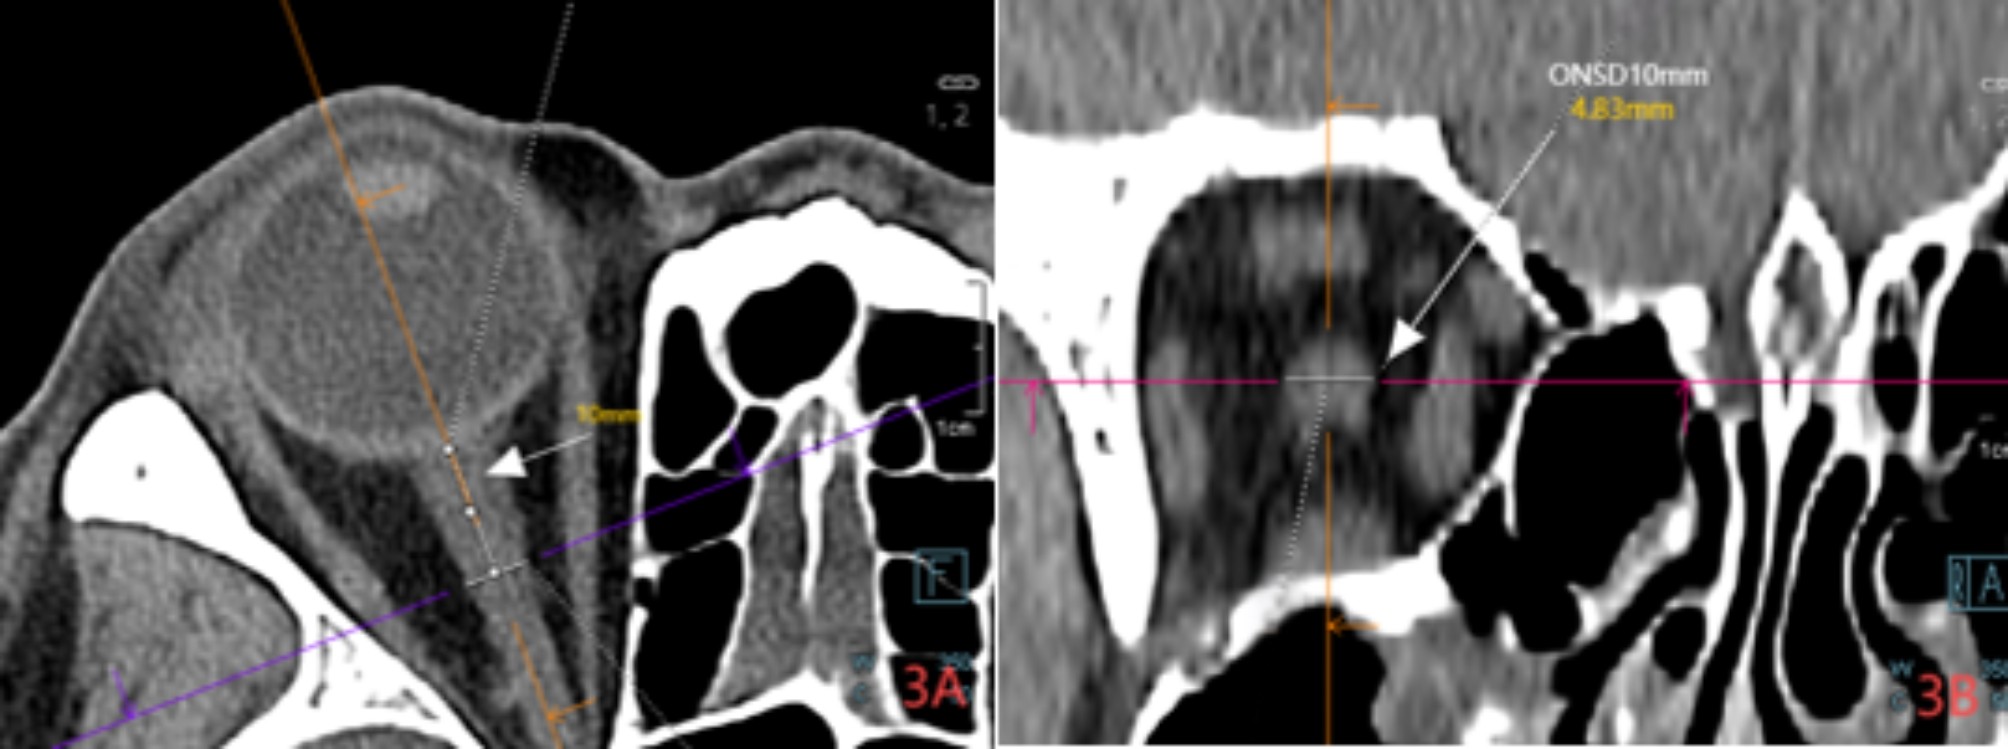

Fig. 3

Axial CT images (A) and coronal images (B) of the brain show the optic nerve sheath, with measurements taken 10 mm behind the eyeball for ONSD values.